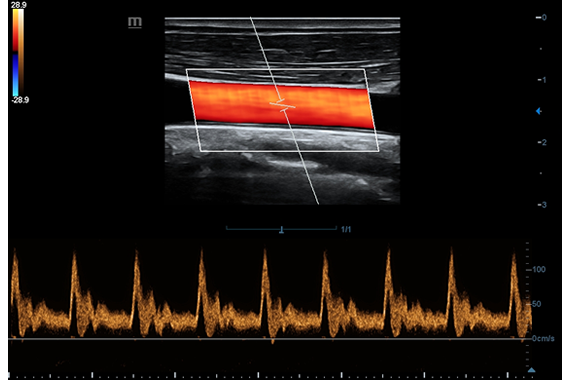

• Поддержка режимов сканирования B/M/Цветовой доплер CDI/Цветной M/Энергетический доплер PD/Направленный энергетический доплер Dir.PD.

• Импульсно-волновой доплер, включая режим высокой частоты повторения импульсов HPRF.

• HR Flow - режим отображения кровотока с высоким временным и пространственным разрешением для точной и однородной визуализации сосудов, в том числе самых мелких.

Цветовой допплер:

Да

Импульсно-волновой допплер:

• HR Flow - режим отображения кровотока с высоким временным и пространственным разрешением для точной и однородной визуализации сосудов, в том числе самых мелких